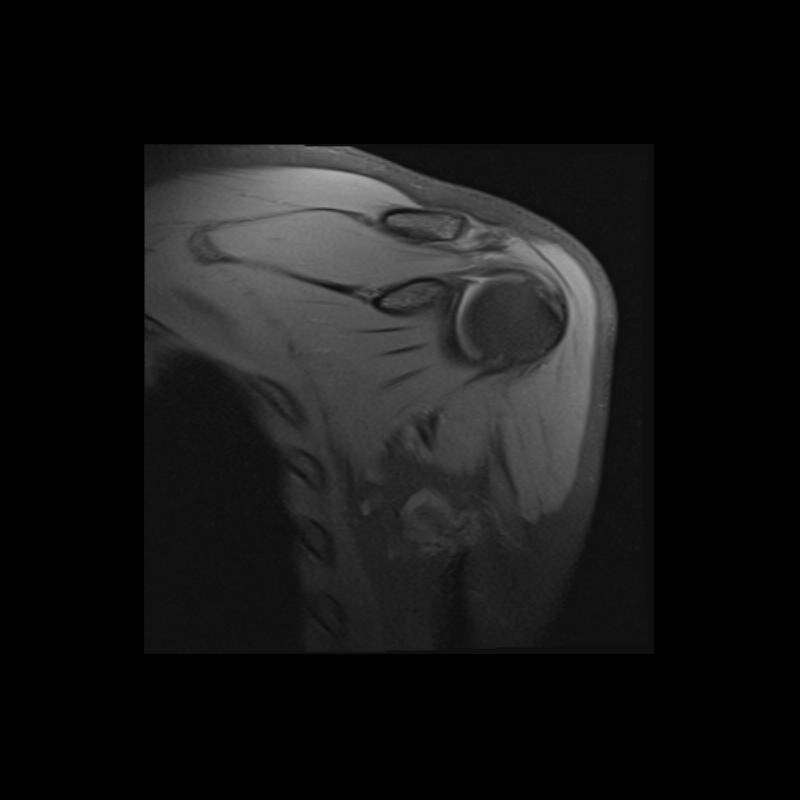

Shoulder MRI Anatomy